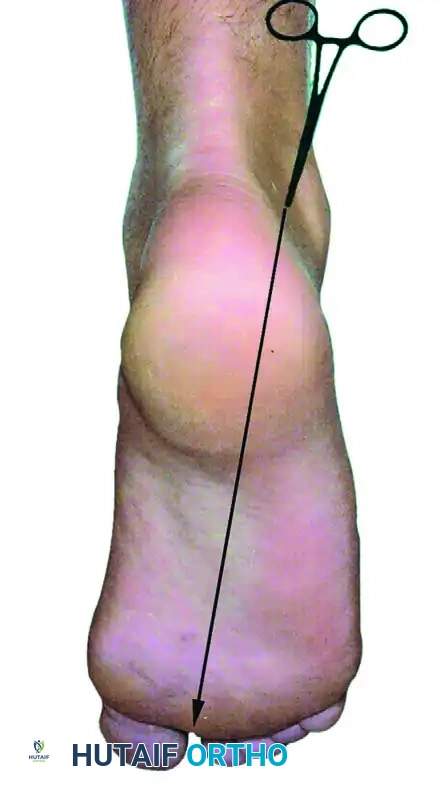

Make the posterolateral portal first. Identify the tip of the lateral malleolus and the lateral border of the Achilles tendon. The portal is placed just superior to a line drawn from the tip of the lateral malleolus to the Achilles tendon, positioned just lateral to the tendon itself.

Make a superficial vertical skin incision using a #11 blade, taking care to incise only the dermis to avoid injuring the underlying sural nerve. Insert a blunt hemostat or a blunt arthroscopic trocar through the skin incision. Aim the instrument anteriorly, directing it along a line pointing toward the first web space of the forefoot. Advance the hemostat bluntly until it firmly hits the posterior bony aspect of the talus or tibia.